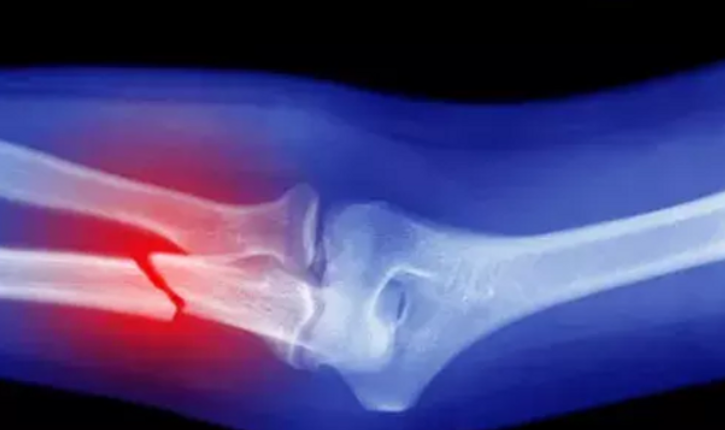

• Vitamina D no previene las fracturas

Vitamina D no previene las fracturas